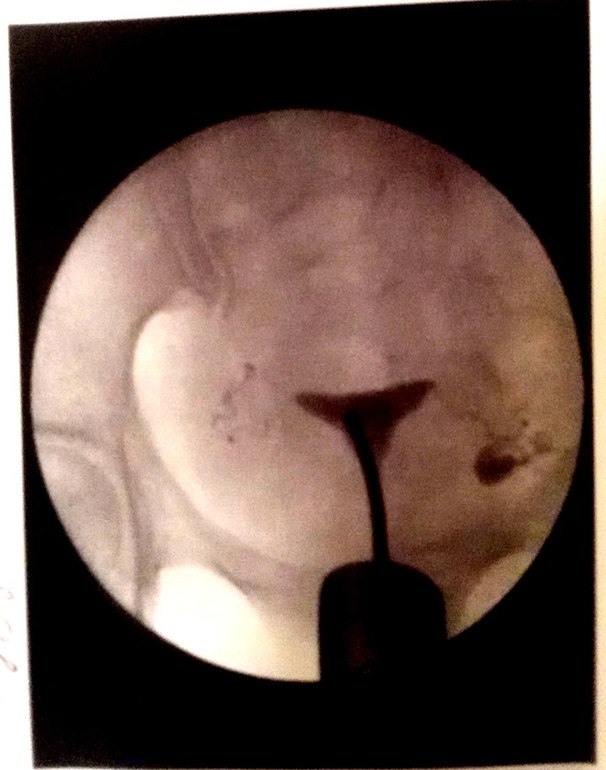

ГСГ Снимок. Кто что думает?

Сделала ГСГ в октябре. Врач сказала все норм. Вчера ходила к другому доктору он мне говорит что правая труба непроходима. На первом снимке самый левый снимок.

На втором снимке правая труба слева.

справа от меня 100% проходима, вышел контраст в брюшную полость

а слева не видно что контраст вышел из трубы, где-то затор

плюсуюсь. слева труба частично проходима, тк контраст по трубе прошел, но почему то не вышел

я не по сторонам а по снимку....

справа проходима видете жидкость вылилась? а с лева не вылилась... значит слева не проходима... то есть правая труба